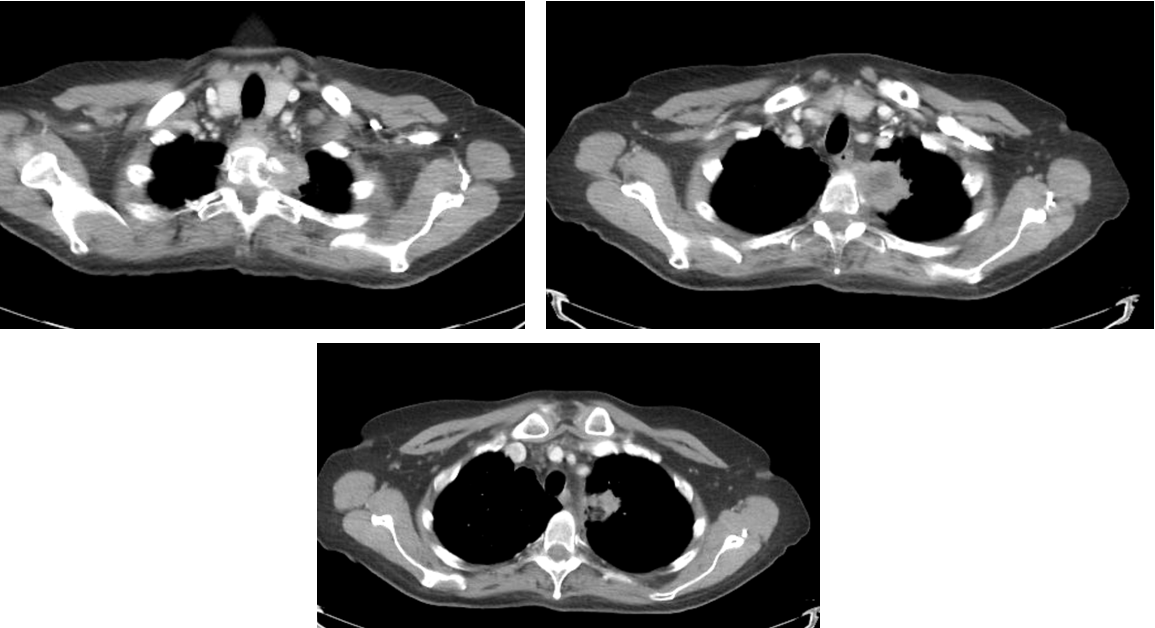

- 75 y/o woman who presented with back pain. On further workup found to have LUL mass with invasion into the vertebral body at T2.

- MRI confirmed vertebral body invasion.

CT Images